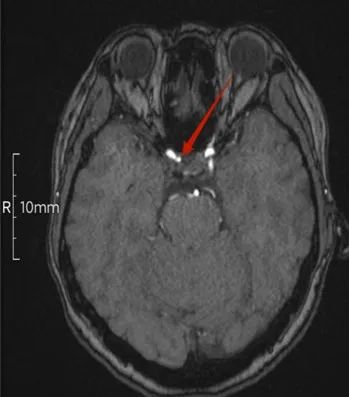

患者李女士,女,44岁,反复头晕2年多,在我院行头颈联合3D-TOF-MRA筛查,发现右侧颈内动脉C7段2.5mm微小动脉瘤。